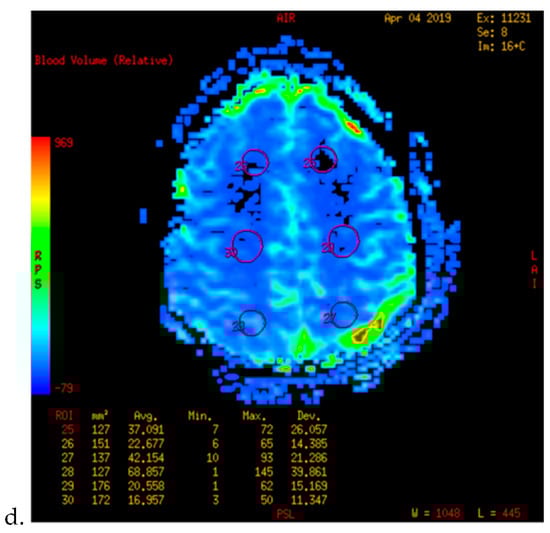

Figure 2.

PWI of patients with TND in the perioperative period after operation (example 2). (a,b) The PWI images of the patients 5 days before operation showed that the cerebral blood flow (CBF) and cerebral blood volume (CBV) of the bilateral hemispheres were basically the same. (c,d) 3 days after the left combined operation, the patients showed blurred vision and dizziness. 6 days after operation, the PWI images showed that the CBF and CBV of the left parietal occipital lobe were significantly higher than those of the opposite side.